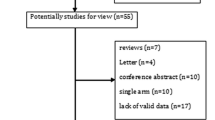

This meta-analysis included a total of 9 studies and 2560 patients [27,28,29,30,31,32,33,34,35]. All patients had completed chemoradiotherapy prior to receiving durvalumab, and no local recurrence or metastasis was present before durvalumab administration. Eight of the studies were retrospective single-arm trials [28,29,30,31,32,33,34,35], while one was a randomized controlled trial [27]. The time interval between completion of radiotherapy and durvalumab administration was reported in 3 studies to be within 1–42 days [27, 32, 33]. The time interval was reported as 0-157 days [28], 1.8–3.7 months [29], 35–981 days [30], 10–84 days [31], ≥ 14 days [34], and 13–103 days [35] in the remaining 6 studies. The study conducted by Girard et al. was indeed excluded from the analysis due to the wide range of interval durations, ranging from 35 to 981 days [30]. This considerable variation raised concerns about whether the 981-day period could still be considered as consolidation therapy. To ensure the credibility of the results, the decision was made to focus on studies with a more consistent and well-defined duration for consolidation therapy. By doing so, the study aimed to improve the reliability and accuracy of the findings. Harada conducted a subgroup analysis, where the time interval was reported as 10–14 days and 14–84 days [31]. The number of patients with pneumonitis (Grade ≥ 3) was reported as 3 and 0, respectively. Pneumonitis grading was evaluated according to the National Cancer Institute Standard Common Terminology for Adverse Events Pneumonia grading criteria. Figure 1 shows the flow diagram, and Table 1 summarizes the basic characteristics of all studies.